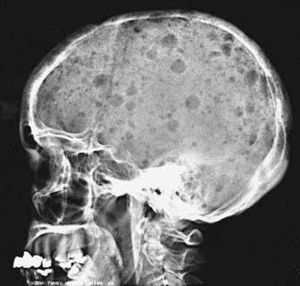

Diagnosis the case??

Multiple myeloma

Punchedout osteolytic lesions (multiple myeloma